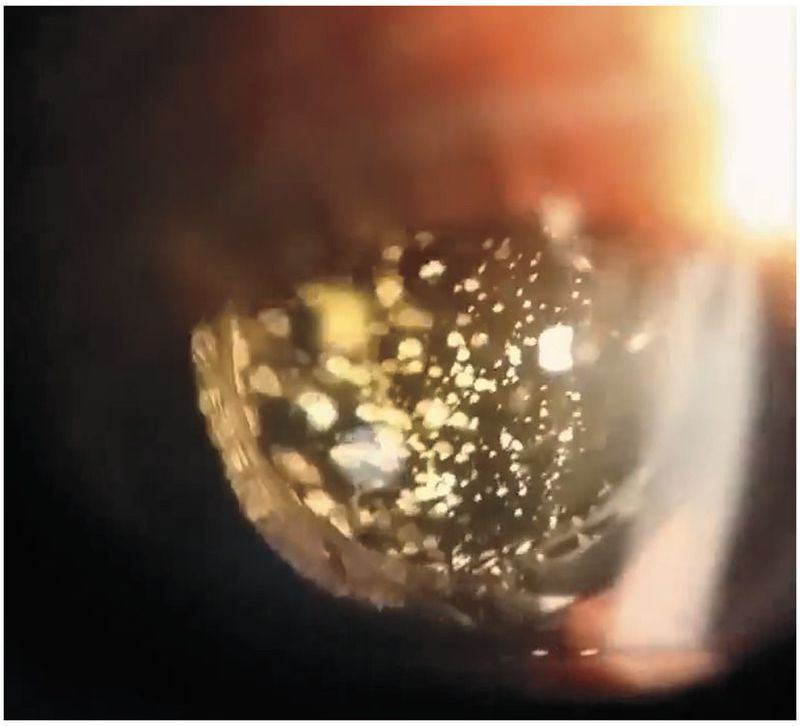

A 54-year-old woman with type 2 diabetes mellitus presented to the ophthalmology clinic for a routine dilated fundus examination. She had a history of cataracts, which had been treated successfully with posterior-chamber intraocular lenses in both eyes. Slit-lamp examination of the left eye revealed multiple sparkling, white, globular, refractile, dotlike opacities in the vitreous cavity. The opacities moved with ocular movement and returned to their original position after movement stopped. The vitreous of the right eye appeared normal. The visual acuity was 20/20 in each eye, and the fundus in each eye was normal. A diagnosis of asteroid hyalosis was made. Asteroid hyalosis is a benign condition that is often unilateral, as in this patient, and is associated with older age. The asteroid bodies are composed of calcium, phosphorus, and various phospholipids. Although asteroid hyalosis may hamper the view of the retina during clinical examination, the visual acuity usually remains unaffected. Given the benign nature of this condition and this patient’s normal visual acuity, no treatment was recommended.